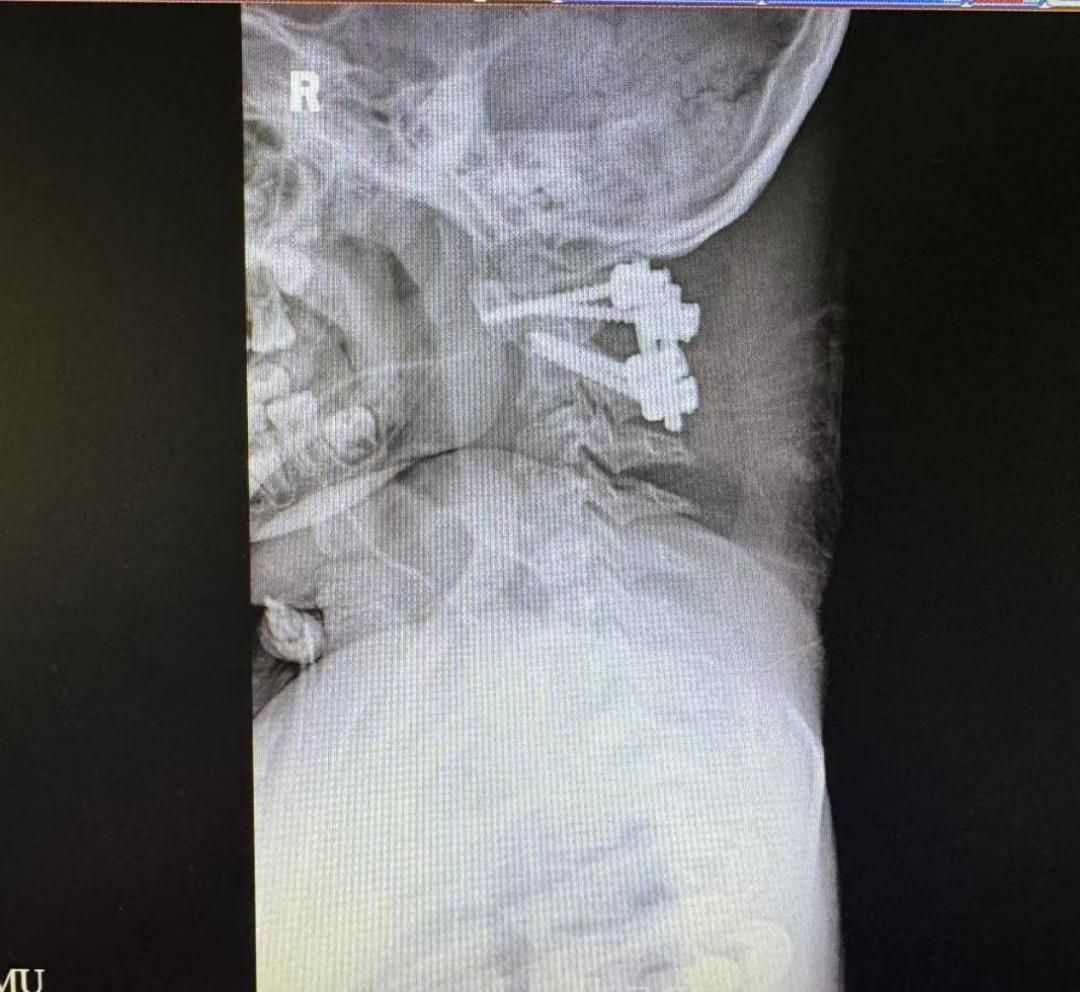

术前术后颈椎X光片

为解决这个问题,脊柱外科一科主任王亮在术前采用3D打印技术复刻了乐乐的寰枢椎模型,反复进行充分的手术模拟。几次模拟下来,王亮有了信心,决定直接实施颈椎后路手术复位手术。术中,团队紧密配合,将手术精度控制在“毫米级”,一次性精准置钉,完成寰枢椎复位与固定。

经院方详细检查后,王亮主任团队发现,乐乐的寰枢椎脱位是由游离齿突引起。虽然从影像学上看没有明显的复位障碍,适合进行后路复位固定手术,但在进一步的颈椎CT检查后,王亮主任团队却发现了棘手的问题:患儿异常细小的颈椎解剖结构使得手术置钉难度倍增。